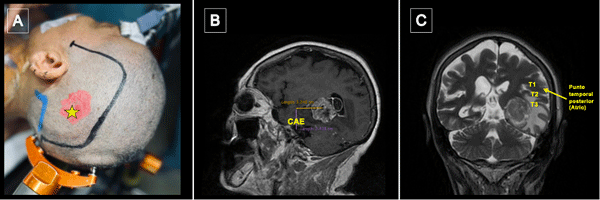

La incisión se centró en el punto temporal posterior (Figura 3), realizándose una herradura frontotemporooccipital izquierda y una cuidadosa hemostasia del colgajo. Craneotomía frontotemporal izquierda. La duramadre fue infiltrada con lidocaína al 1%. Posterior a ello se efectuó una durotomía arciforme con pedículo hacia basal exponiendo el giro temporal superior y medio. Con la paciente despierta se hizo ecografía intraoperatoria para delimitación de los márgenes tumorales, los cuales se identificaron con “tags” (Figura 4).

Figura 3.Punto temporal posterior, posicionamiento. A) Posicionamiento de la cabeza del paciente en cabezal de Mayfield Marcación de incisión centrada en punto temporal posterior (estrella amarilla). B) Se toma como referencia anatómica el conducto auditivo externo (CAE) para medición de punto temporal posterior. C) El punto temporal posterior corresponde topográficamente con el atrio del ventrículo lateral.